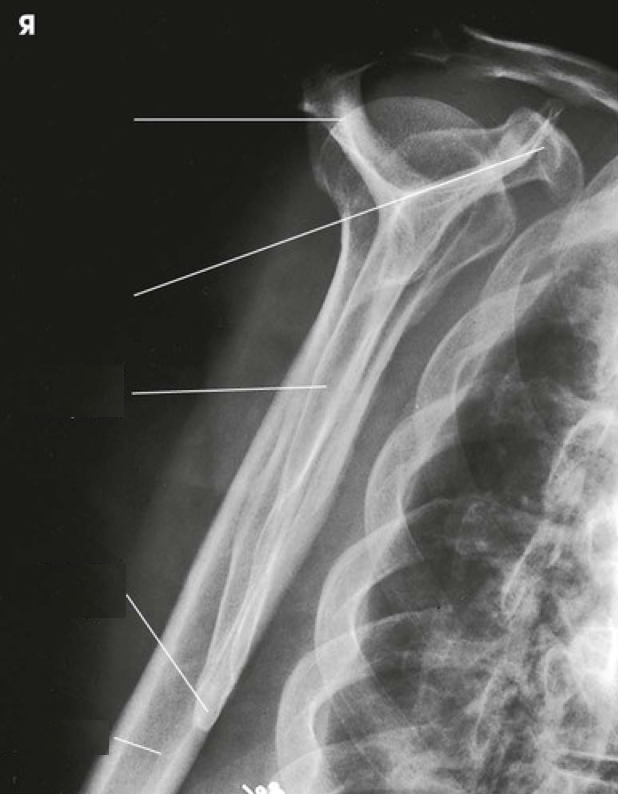

Question 12

Question

Label the image

Image:

c91d01a3-048a-41fe-a502-16f316f7c8ee (image/png)

Answer

lesser tubercle

humerus

coracoid process

acromioclavicular joint

clavicle

scapulohumeral joint

acromion